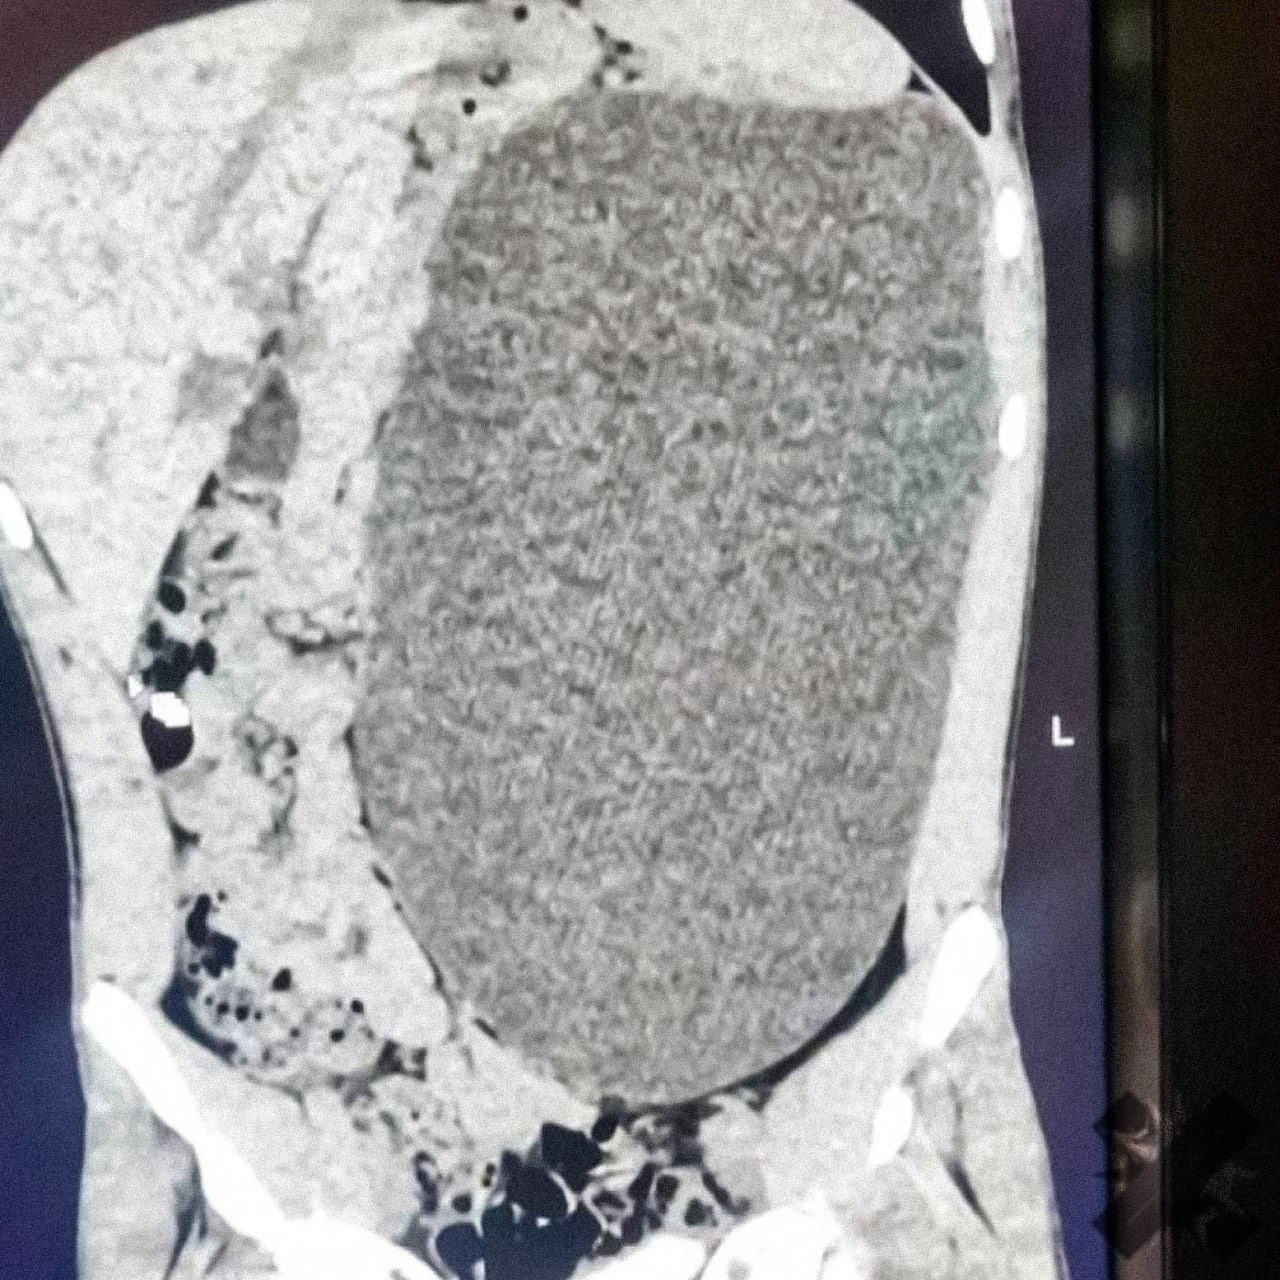

В Новосибирске у подростка удалили почку размером с пятилитровую бутылку Как отметили в больнице это была настоящая бомба замедленного действия случайный удар в живот и мешок мог разорваться До обследования подросток не испытывал никаких симптомов и считал себя полностью здоровым Фото Telegram канал Министерства здравоохранения Новосибирской области

Почка размером с пятилитровую бутылку выросла у подростка Образование заняло почти весь живот и сдавливало внутренние органы При этом 17 летний парень из Новосибирска не чувствовал никаких симптомов и считал себя абсолютно здоровым Любой сильный удар в живот мог закончиться очень плохо Четыре дня врачи откачивали жидкость а затем удалили поражённую почку сейчас подросток идёт на поправку НМШ

У подростка обнаружили почку размером с пятилитровую бутылку Она занимала почти весь живот и сдавливала остальные органы 17 летний новосибирец не испытывал никаких симптомов и считал себя полностью здоровым Врачи нашли патологию случайно и назвали её бомбой замедленного действия случайный удар по животу мог привести к разрыву этого образования В течение четырёх дней хирурги откачивали скопившуюся жидкость а затем удалили поражённую почку Сейчас пациент идёт на поправку хорошо что всё закончилось благополучно Подпишись на Ленту дня в MAX Участвуй в розыгрыше